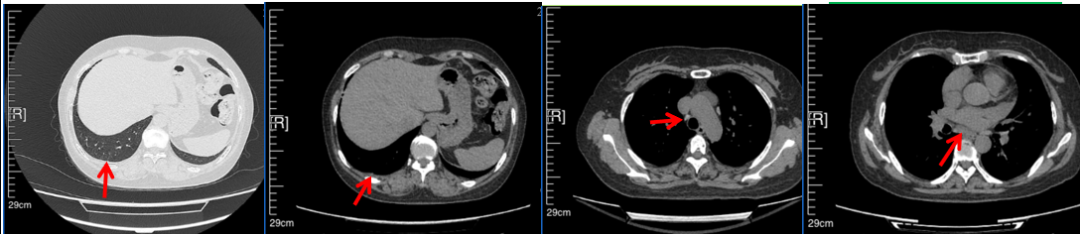

56岁,女性,无吸烟史饮酒史,既往体健。2023年02月患者体检发现肺占位性病变,胸部增强CT:右肺下叶后基底段结节;右侧锁骨上及纵隔内多发淋巴结肿大。PET-CT:右肺下叶周围型肺癌可能性大;1R、2L、3P、4R、4L及7组淋巴结转移可能性大。2023年02月就诊于本院胸外科行超声胃镜下纵隔肿物穿刺活检术,病理:结合免疫组化,符合肺腺癌。行NGS基因检测:EML4:exon20-ALK:exon20融合。PD-L1(克隆号22C3)TPS=55%。

2023年2月20日基线检查

2024年6月复查PR(最佳疗效)

2024年12月复查维持PR

2025年3月复查维持PR